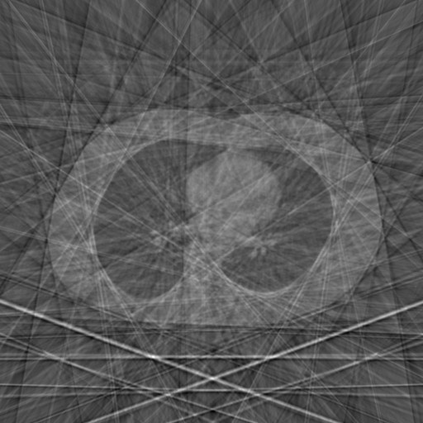

Sparse-view computed tomography (CT) -- using a small number of projections for tomographic reconstruction -- enables much lower radiation dose to patients and accelerated data acquisition. The reconstructed images, however, suffer from strong artifacts, greatly limiting their diagnostic value. Current trends for sparse-view CT turn to the raw data for better information recovery. The resultant dual-domain methods, nonetheless, suffer from secondary artifacts, especially in ultra-sparse view scenarios, and their generalization to other scanners/protocols is greatly limited. A crucial question arises: have the image post-processing methods reached the limit? Our answer is not yet. In this paper, we stick to image post-processing methods due to great flexibility and propose global representation (GloRe) distillation framework for sparse-view CT, termed GloReDi. First, we propose to learn GloRe with Fourier convolution, so each element in GloRe has an image-wide receptive field. Second, unlike methods that only use the full-view images for supervision, we propose to distill GloRe from intermediate-view reconstructed images that are readily available but not explored in previous literature. The success of GloRe distillation is attributed to two key components: representation directional distillation to align the GloRe directions, and band-pass-specific contrastive distillation to gain clinically important details. Extensive experiments demonstrate the superiority of the proposed GloReDi over the state-of-the-art methods, including dual-domain ones. The source code is available at https://github.com/longzilicart/GloReDi.